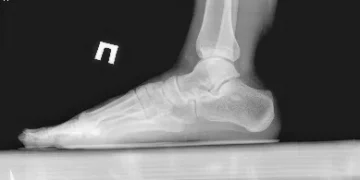

- Процедура визуализирует состояние костей и суставов стопы и лодыжки.

Рентген стопы является важным диагностическим методом, который позволяет выявлять различные патологии и травмы в данной области. При проведении рентгенографии стопы я всегда обращаю внимание на правильную позицию пациента, так как это напрямую влияет на качество снимка. Особое внимание следует уделять лучам, которые должны проходить перпендикулярно к плоскости снимка, что способствует получению более четкого изображения костей и суставов.

Одной из главных причин, по которой я рекомендую рентген стопы, является его высокая информативность при диагностице переломов, вывихов и разных заболеваний, таких как артрит или плантарный фасциит. На рентгеновских снимках легко заметить деформации, которые могут указывать на наличие хронических заболеваний. Кроме того, рентген помогает в оценке состояния после проведенных операций или травм, позволяя отслеживать процесс заживления и восстановление функции стопы.

Врач может получить полное представление о здоровье стопы пациента, анализируя несколько рентгеновских изображений, сделанных под разными углами, как в состоянии покоя, так и при определенной нагрузке. Существует три основных типа рентгенологического обследования стопы, каждый из которых помогает выявить различные патологии:

Боковая проекция стопы может быть выполнена несколько раз. В первом снимке врач фиксирует состояние стопы без нагрузки, а во втором – с нагрузкой. При этом пациент должен занять специальную позицию, вставая на одну ногу, которая будет исследоваться рентгенологически. Сравнительный анализ двух изображений, характеризующих состояние стопы с и без нагрузки, позволяет доктору оценить динамику состояния стопы, выявить проблемы с суставами и диагностировать, например, плоскостопие.